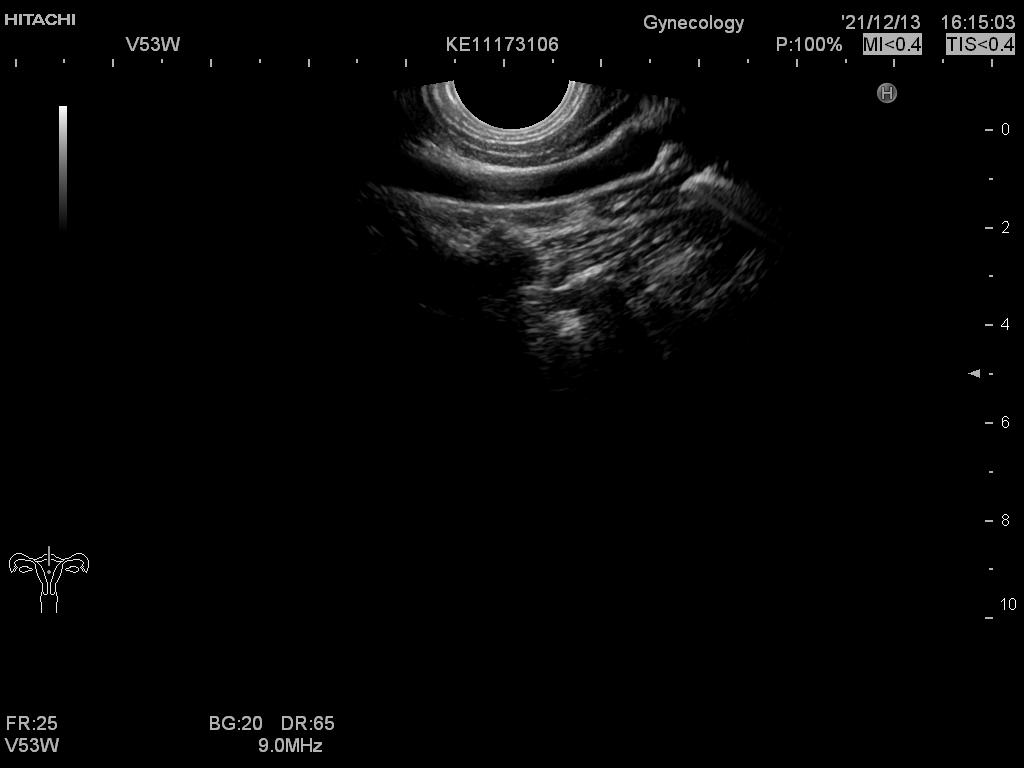

Hitachi EUP-V53W Endocavity Vaginal – HI VISION

Frequency Range: 8 – 4 MHz

Hitachi EUP-V53W Endocavity Vaginal – HI VISION for Endovaginal

Compatible with Hitachi Hi Vision systems

| Radiology functions | Contrast Harmonic Imaging (CHI), Elastography (RTE), RT Sonography (RVS) |